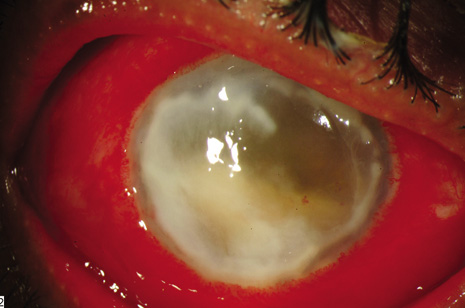

The visual outcomes after treatment of posttraumatic endophthalmitis are generally worse than the other endophthalmitis categories. In addition to vitreous infiltrates and hypopyon, other signs of posttraumatic endophthalmitis include exudate around foreign body and retinal periphlebitis (Fig. 10). In the National Eye Trauma System21 review of endophthalmitis after penetrating injuries with retained intraocular foreign bodies, 9 of 22 (40.9%) culture positive cases achieved 20/400 or better visual acuity. Either Bacillus or staphylococci species were isolated in 21 of these 22 (95%) culture-positive cases. Endophthalmitis was much less likely to develop in eyes with primary repair within 24 hours of the injury (10/287 or 3.5%) than in eyes with primary repair more than 24 hours after the injury (22/164 or 13.4%; p < 0.0001). Major reasons for the poor visual acuity outcomes in these cases are the marked structural damage to the eye resulting from the initial injury, the delay in the primary wound repair, and the greater virulence of the organisms commonly associated with the traumatic endophthalmitis. Bacillus species, most commonly B. cereus, are cultured from 28% to 46% of eyes with posttraumatic endophthalmitis.20,21,105 Bacillus species are ubiquitous, aerobic, gram-positive, spore-forming rods. Endophthalmitis caused by Bacillus species is characterized by a rapidly progressive course, ring corneal infiltrates (Fig. 11), and, generally, a poor visual outcome even with prompt therapy (Fig. 12).105–109

Fig. 11. Endophthalmitis caused by Bacillus cereus and a retained intraocular foreign body. Note the prominent conjunctival congestion, corneal ring infiltrate, and dense hypopyon. Visual acuity was light perception. Despite prompt treatment, enucleation was eventually performed because of the blind, painful eye.